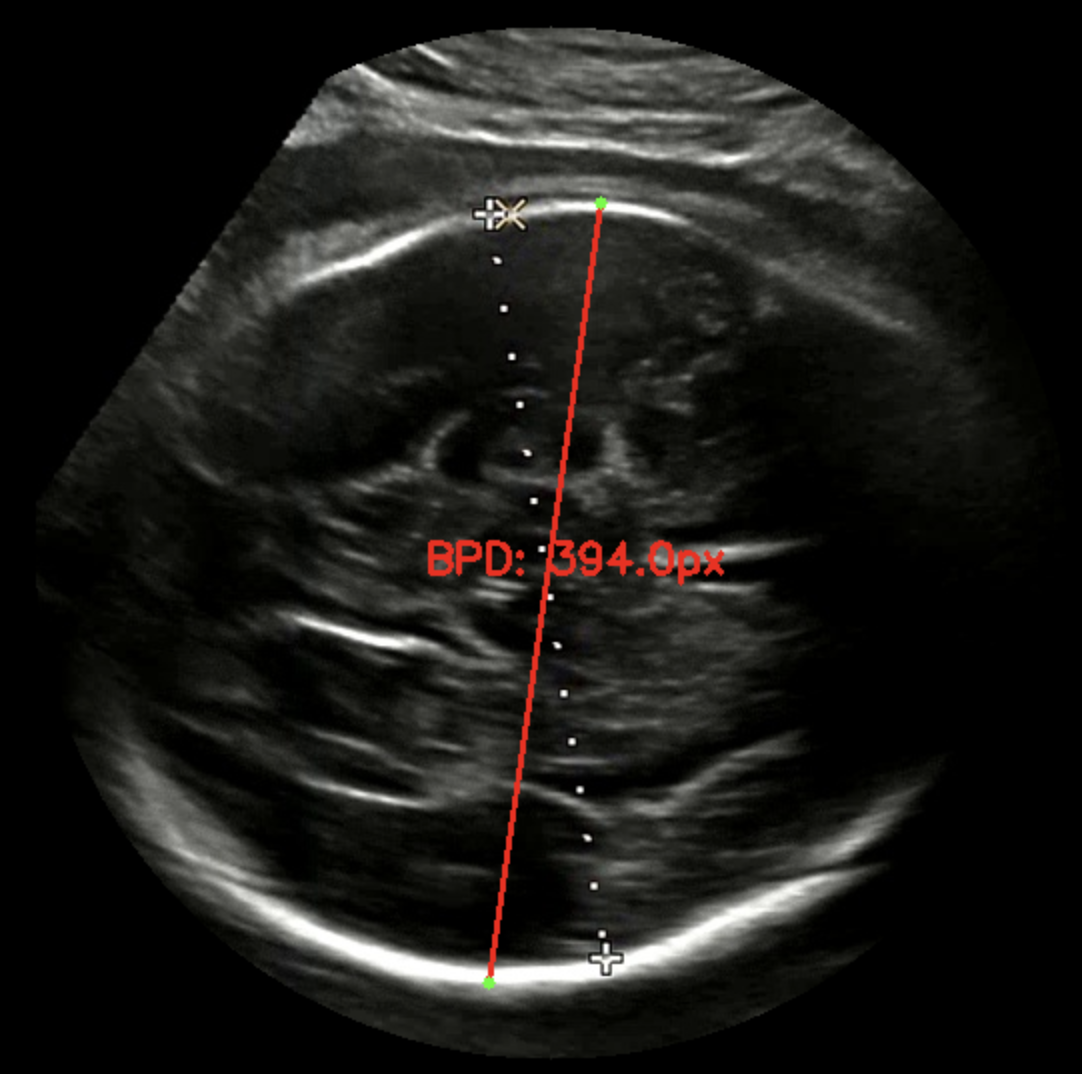

대부분의 녹화본에는 스케일바가 있다. 여기서 픽셀 당 실제거리 (cm/pixel) 을 구할 수 있다고 판단했다. 그래서 내가 원하는 두 점 사이의 거리 (단순 픽셀 거리) 곱하기 cm/pixel 을 곱하면 실제 거리를 구할 수 있다고 생각했다. cm/pixel 이 배율인 셈이다.

실제로는 8.22 cm 로 기록되었고 내가 측정한 기록값은 8.29 cm 로 오차는 크지 않았다. 가설을 검증했고 충분히 해볼 만하고 생각했다. 다만 아래와 같은 해결 과제가 남았다. 첫 번째는 계산 시 (14 cm / 스케일 바 픽셀 거리) 로 하드코딩해서 배율을 계산했기 때문에 스케일 바를 검출하는 이미지 전처리 과정이 필요했다. 두 번째는 초록색 영역 검출 시 곡선과 같은 형태 두 개를 찾고 그 사이 거리를 찾는 식이라 이미지별로 다소 편차가 있었다. 내 눈에는 원처럼 보이는데 컴퓨터가 인식할 때는 원으로 인식하지 않아서 반원 곡선 형태를 찾도록 코딩했다.